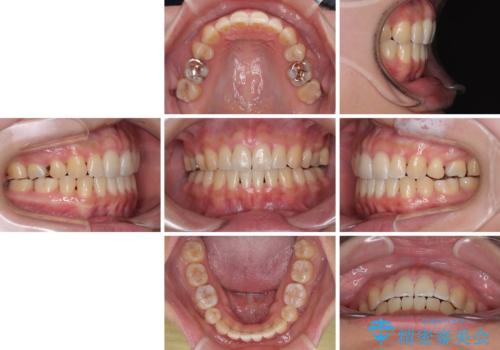

欠損と口元の突出感 ワイヤー装置での抜歯矯正

- 1年10ヶ月

- 下顎小臼歯が欠損しており、さらに上顎が全体的に突出していることを気にして来院された患者様です。

下顎は片方の小臼歯が欠損していたため、正中がずれた上に、上下前歯が接触していない状態でした。

上顎左右の小臼歯2本および下顎小臼歯を1本抜歯し、補助装置を用いて上顎大臼歯が前方に移動しないように固定した上で、ワイヤー装置にて矯正治療を行うこととしました。